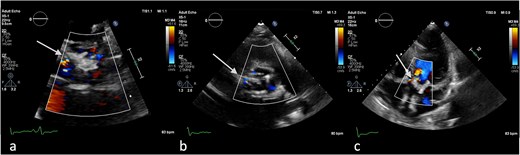

On the third day of hospitalization, transesophageal echocardiography revealed only moderate mitral regurgitation (Videos 3 and 4). However, on day 11, follow-up echocardiography showed a 7 × 18 mm vegetation on the prosthetic aortic valve, with a 5 × 7 mm floating formation (Fig. 2, Videos 5 and 6). By day 21, the vegetation had progressed, with a new formation on the tricuspid valve, an aortic annulus abscess, and worsened mitral regurgitation to severe (Figs 1 and 3, Videos 7 and 8). The development of double-sided endocarditis is very rare, and since the patient experienced it twice, congenital predisposing factors such as Patent Foramen Ovale and ventricular septal defects were ruled out. It was hypothesized that multiple predisposing factors ultimately led to the reinfection. Active IV drug use and its potential immunosuppressive effects, along with persistent poor dental condition and recurrent cutaneous infections, were identified as the main contributors, in addition to the patient’s overall non-adherence, for the development of double-sided endocarditis on two occasions.

Antero-septal paravalvular leak (PVL) of the prosthetic aortic valve in TTE (a) TTE PLAX (b), PSAX (c) 5CV (day 21 of hospitalization).